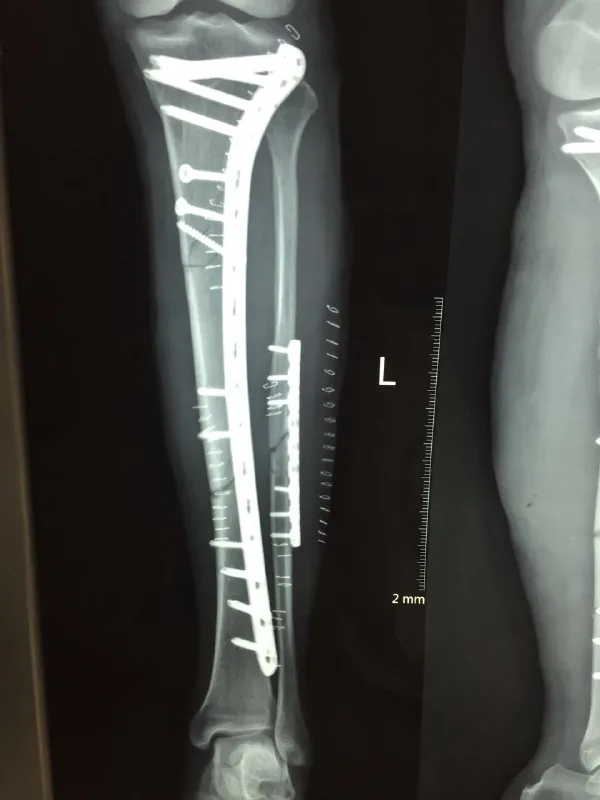

影像学检查是胫腓骨骨折诊断的重要方法,包括X线平片和CT检查。X线是骨折首选检查手段,可明确骨折线的位置及类型;CT则适用于复杂的关节内骨折或评估骨折合并脱位的患者。

对于较为复杂的胫腓骨骨折则多采用手术内固定治疗,如内固定钉板或髓内钉技术。手术治疗可迅速恢复骨折端的解剖结构与生物力学功能,但需注意手术后护理和感染控制问题。